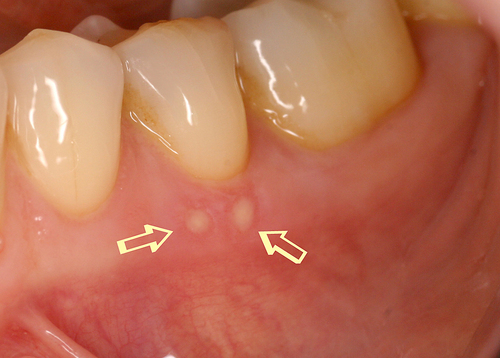

Par exemple, sur des aphtes douloureux (fig. 20) un rayonnement laser est rapproché progressivement jusqu’à une disparition quasi complète des sensibilités (fig. 21).

Fig.20 Présence de deux aphtes douloureux